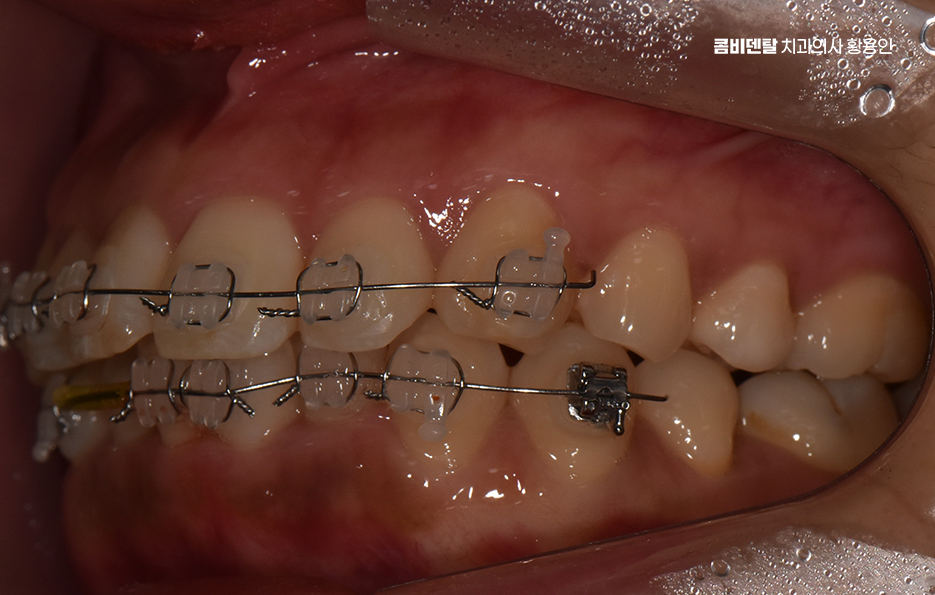

앞니 부분 교정이라는 건 말 그대로 전체 치아를 전반적으로 움직이는 게 아니라, 웃을 때 보이는 앞니 위주로 배열이나 틀어짐, 벌어짐 등을 정리하는 방식으로 앞니 부분 교정은 치료 시간과 비용, 교정 장치에 대한 부담을 줄일 수 있어서 치료가 가능한 케이스에 해당된다면 앞니를 전체교정에 비해 빠르게 개선할 수 있어요

앞니 부분 교정은 단순히 환자분이 원한다고 선택 가능한 것은 아니며 앞니만 따로 움직일 수 있을 만큼 주변 치아나 교합 상태가 안정적인 경우여야만 적용이 가능한 거예요.

그래서 단순히 앞니 사이가 벌어졌거나, 살짝 돌아가 있거나, 비대칭으로 삐뚤어진 경우처럼 부분적인 배열 문제일 때, 즉 전체적인 교합이나 턱의 위치에는 큰 문제가 없고 미세한 심미적인 조정이 필요한 경우에만 앞니 부분 교정이 효과적으로 작용한다고 볼 수 있어요

그런데 앞니만 건드리는 교정이라 하더라도 치아는 전체적으로 연결돼 있기 때문에, 단순히 눈에 보이는 앞니만 보고 ‘이건 부분 교정으로 되겠지’라고 판단하면 오히려 문제가 생길 수 있어서 앞니 부분 교정도 사전에 정밀한 진단이 필수이고 전체적인 교합 상태, 위아래 치열의 중심선이 맞는지, 앞니의 돌출 각도나 회전 상태, 잇몸뼈의 두께나 여유 공간 등을 모두 고려해서 가능 여부를 판단해야 하는 거예요

부분교정이 가능하다고 결론이 나면, 그때부터 어떤 방식으로, 얼마나 오랜 시간 동안 치료할 수 있을지 구체적인 계획을 세우게 되는 것이고 여기서 중요한 건, 부분 교정이라고 해서 모든 케이스가 간단하게 끝나는 건 아닌데 보통 3개월에서 6개월 정도면 끝난다고 하지만, 케이스에 따라 8개월 이상 걸리는 경우도 있고 유지 장치 착용도 고려하면 그저 단기 치료로만 끝나는 것은 아니기 때문에 치료 전에 교정 전문의와 충분히 먼저 상의가 필요한 거예요